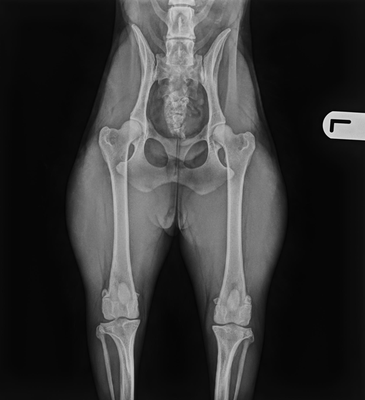

Hip & Elbow x-rays

Perhaps one of the most well known health testing in dogs, hip and elbow x-rays taken to check for signs of dysplasia. Once taken by a qualified vet the x-rays are then sent to a scoring board dependent on country of residence or personal choice of the breeder. To the right, is a comparison of the results across the most common available testing organisations.

The organisation which we primarily use for our program is BVA.

Elbows: Elbows are graded individually with a score from 0-3 on each side. The ideal being a score of 0. To have an elbow scored there must be at least two x-rays; flexed lateral and neutral view. Elbow dysplasia is uncommon in both Komondor and Mudi.

Hips: Under the BVA scheme, the marking of hips is broken down into 9 sections, the maximum marks in any one section is 6, and the maximum overall is 106. The aim is to obtain the combined lowest number possible, the best result possible being a 0. Please view the example images of our dogs results attached above to see the 9 possible sections.